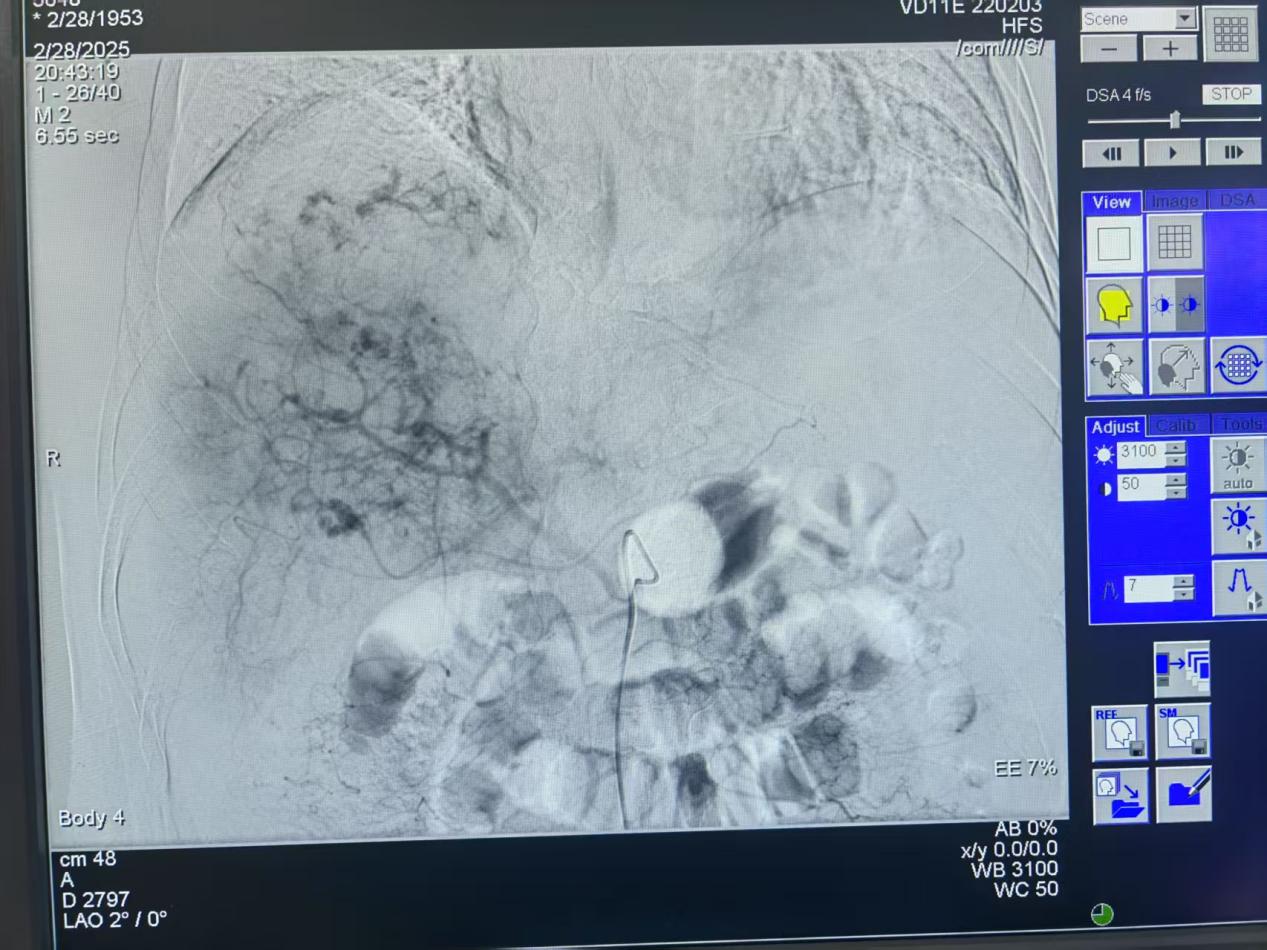

術(shù)前患者肝臟血管造影圖片

術(shù)后患者肝臟血管造影圖片